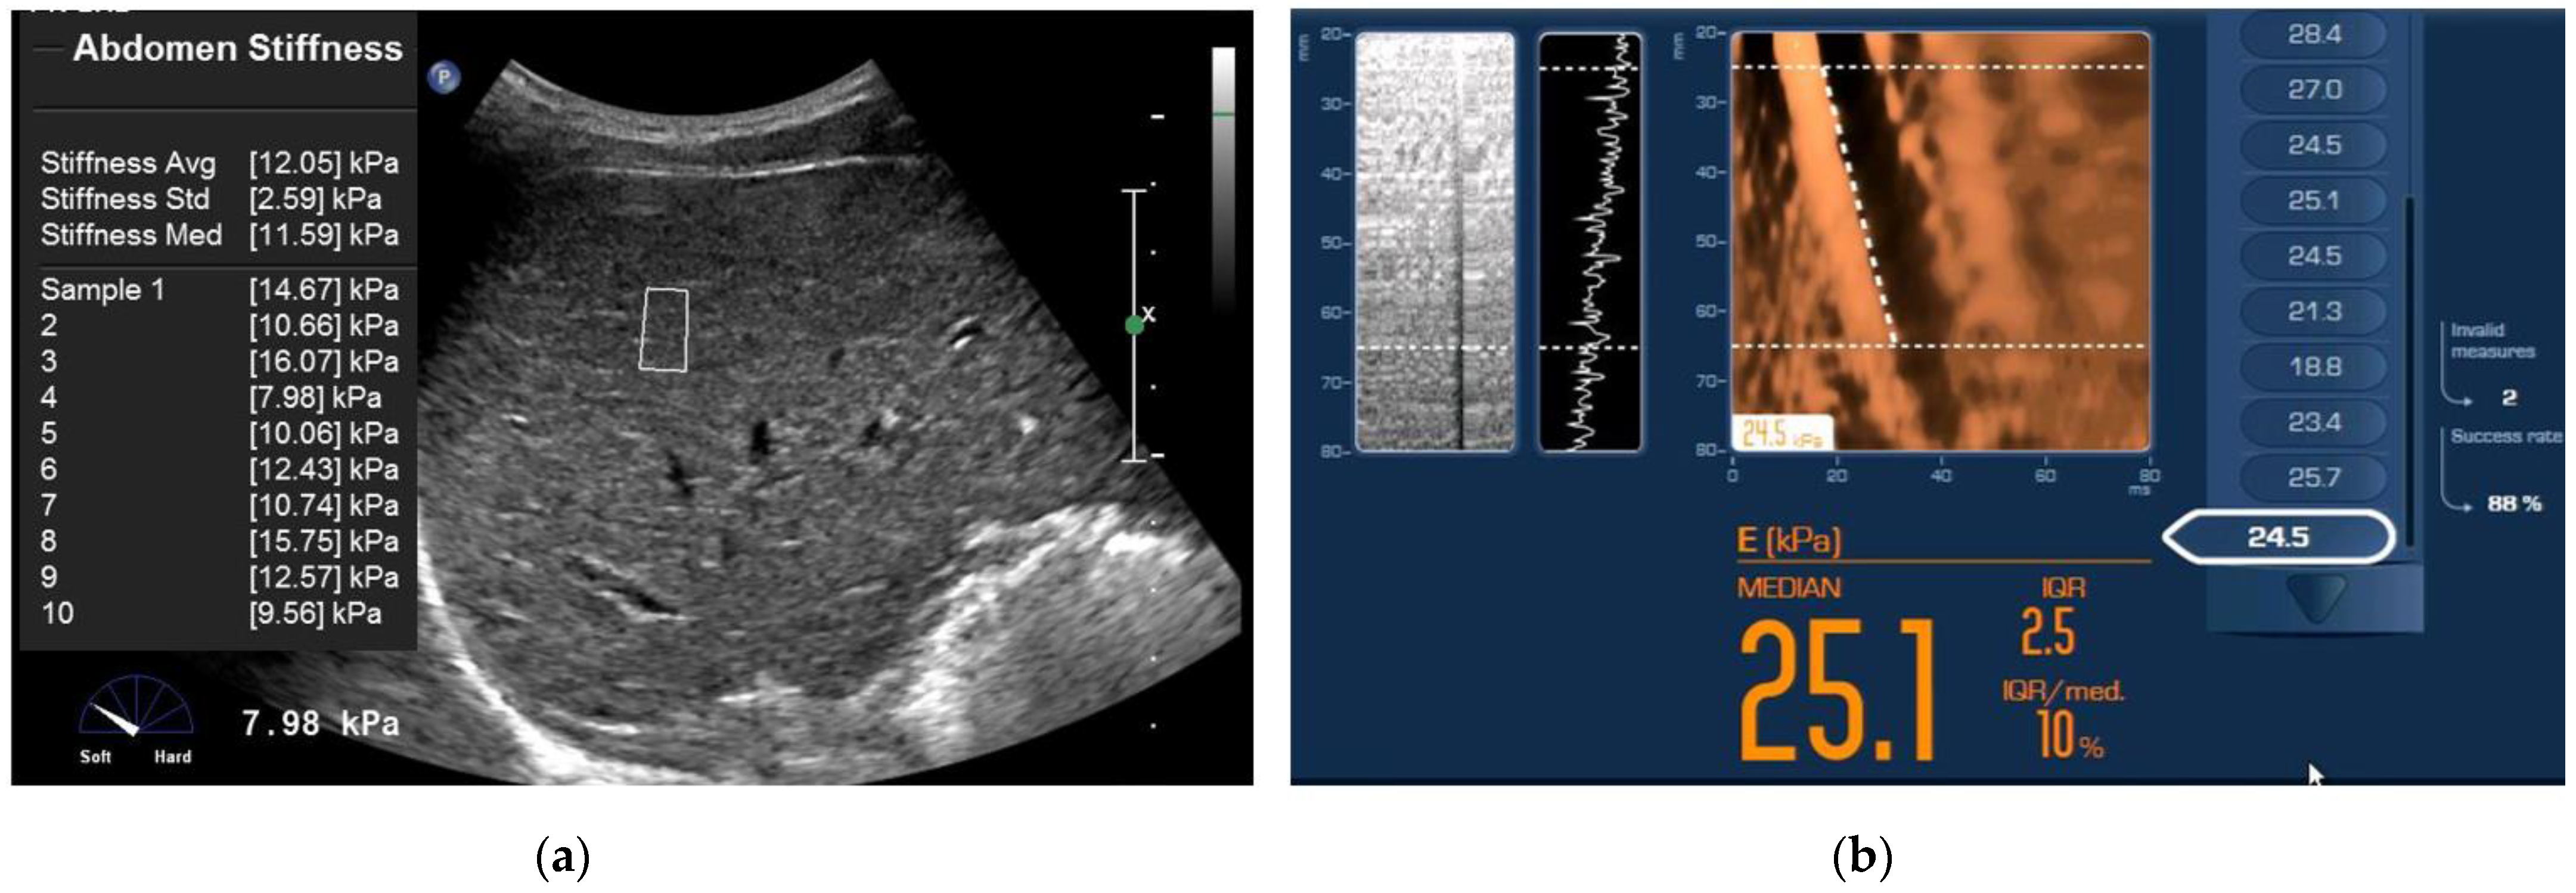

2.2. Point Shear Wave Elastography (ElastPQ)

2.3. Transient Elastography (TE)